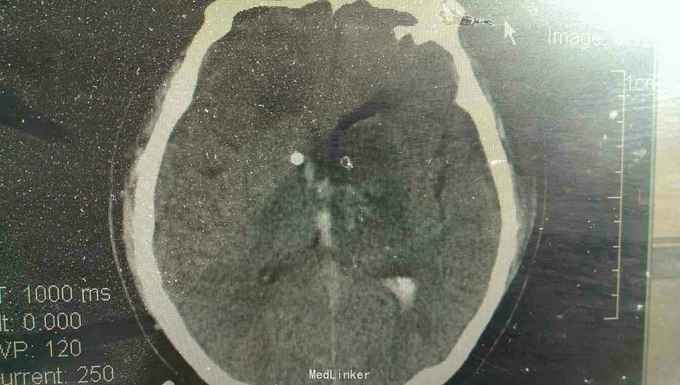

患者男性,56岁。以突发头痛伴意识不清半小时入院。患者入院半小时前突然自觉头痛,性质剧烈,呕吐多次,随即意识不清。来我院就诊。

浅昏迷状态,无语言。刺激后右侧肢体不动,左侧肢体可动。双侧瞳孔等大正圆,直径3.0毫米,光反射迟钝。右侧病理反射阳性。

脑出血,高血压病 急诊行微创硬通道内镜下血肿清除术,术中清除大部分血肿,患者术后第二天清醒右侧肢体三级,语言迟缓。